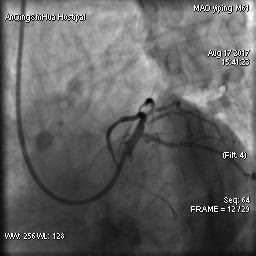

毛先生的血管在心臟左主干體部及分叉部都出現(xiàn)嚴(yán)重狹窄,僅一絲血流通過(guò),前降支的血流已明顯減慢。難怪日常步行都會(huì)引起心絞痛,毛先生隨時(shí)都可能心臟驟停。

術(shù)前 心臟左主干末端嚴(yán)重狹窄